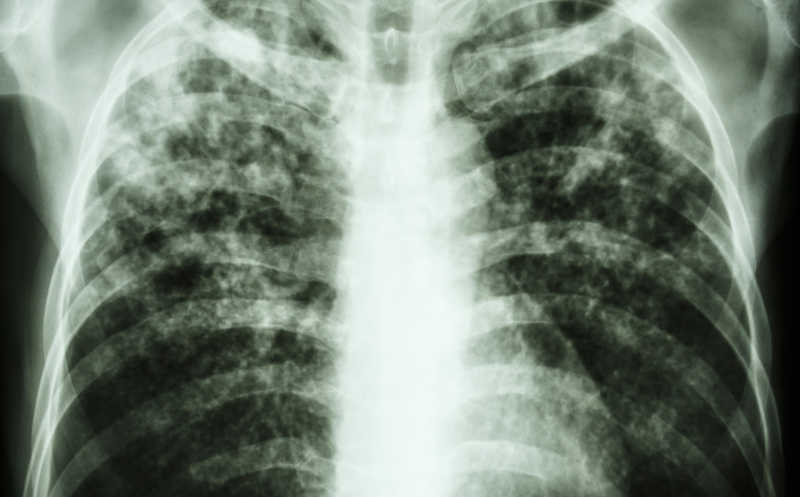

Туберкулез остается одной из ведущей причин смерти от инфекций. Один из принятых в клинической практике методов борьбы с мультирезистентным туберкулезом — режим BPaLM, состоящий из четырех препаратов. Одно из лекарств — линезолид — ВОЗ ввела в схему в 2022 году, что позволило сократить длительность лечения втрое (шесть месяцев вместо изначальных 18). Однако линезолид обладает высокой токсичностью и плохо переносится многими пациентами. В The Lancet Infectious Diseases опубликованы результаты исследования его аналога — дельпазолида. Этот препарат не только проявляет сильную антимикробную активность, но и обладает куда лучшим профилем безопасности, чем линезолид.

Дельпазолид — ингибитор бактериальных рибосом — протестировали в клиническом исследовании фазы 2b PanACEA-DECODE-01, которое проводилось в Танзании и Южной Африке. Для участия набрали 76 взрослых (от 18 до 65 лет) людей с легочной формой туберкулеза. Их разделили на пять равных групп, которые отличались по дозировке дельпазолида: 400 мг раз в сутки, 800 мг раз в сутки, 1200 мг раз в сутки или 800 мг дважды в сутки. Пятая группа была контрольной и ее участники не получали дельпазолид. Помимо этого, всем пациентам назначили одинаковую схему бедаквилина, деламанида и моксифлоксацина. Лечение проводили 16 недель, а общее время наблюдения составило 52 недели. За это время все участники четыре раза проходили обследование, в ходе которого у них брали анализ крови на показатели печени и почек, а также собирали образцы мокроты, чтобы определить присутствие Mycobacterium tuberculosis — возбудителя инфекции.